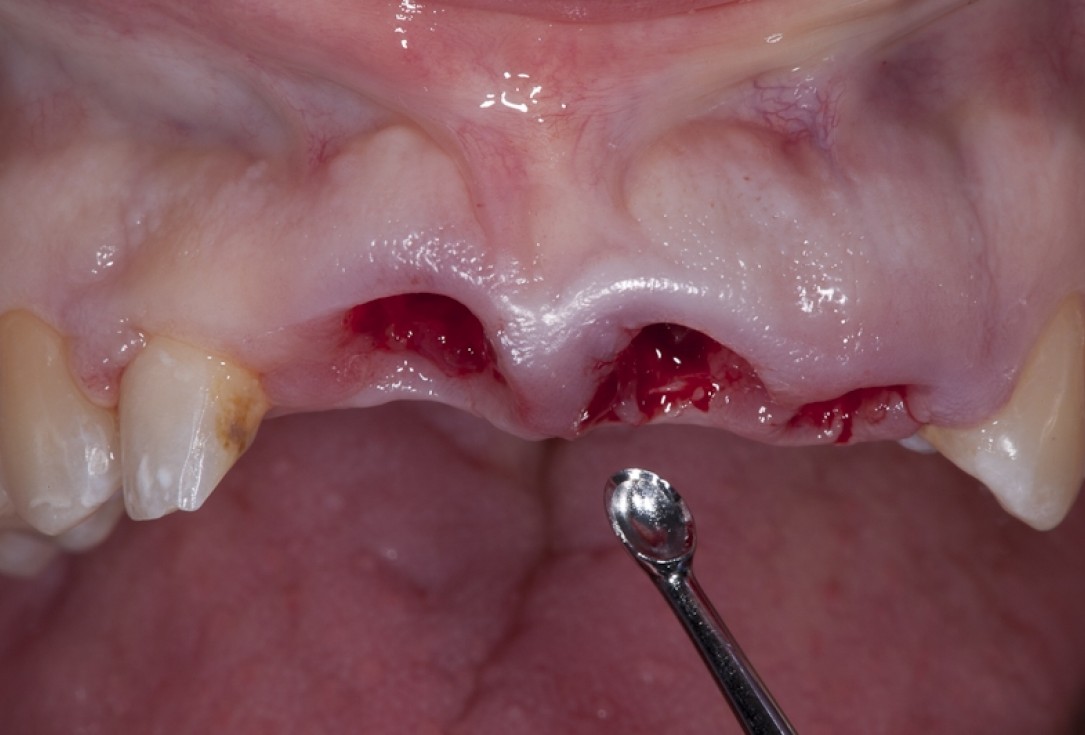

Socket preservation with permamem® - Dr. R. Rannula

Situation after tooth extraction.